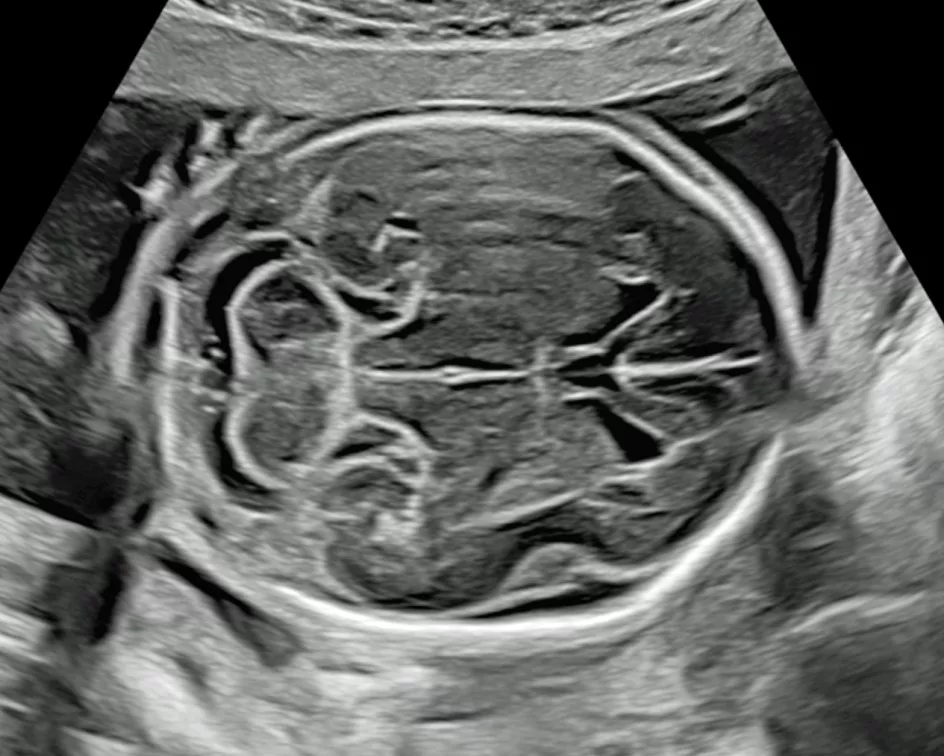

​L’image du fœtus est obtenue après un traitement informatique de la propagation à travers les tissus maternels des ultrasons émis et recueillis par la sonde d’échographie.

L’image du fœtus peut être obtenue soit à travers la paroi abdominale maternelle, soit à travers sa paroi vaginale.

Il s’agit d’une image virtuelle, correspondant à une réalité transformée par les ultrasons et le traitement informatique de l’image. L’échographe n’est pas une caméra, et ne permet pas de « voir le bébé ».

• échocardiographie,

• neuro-imagerie,